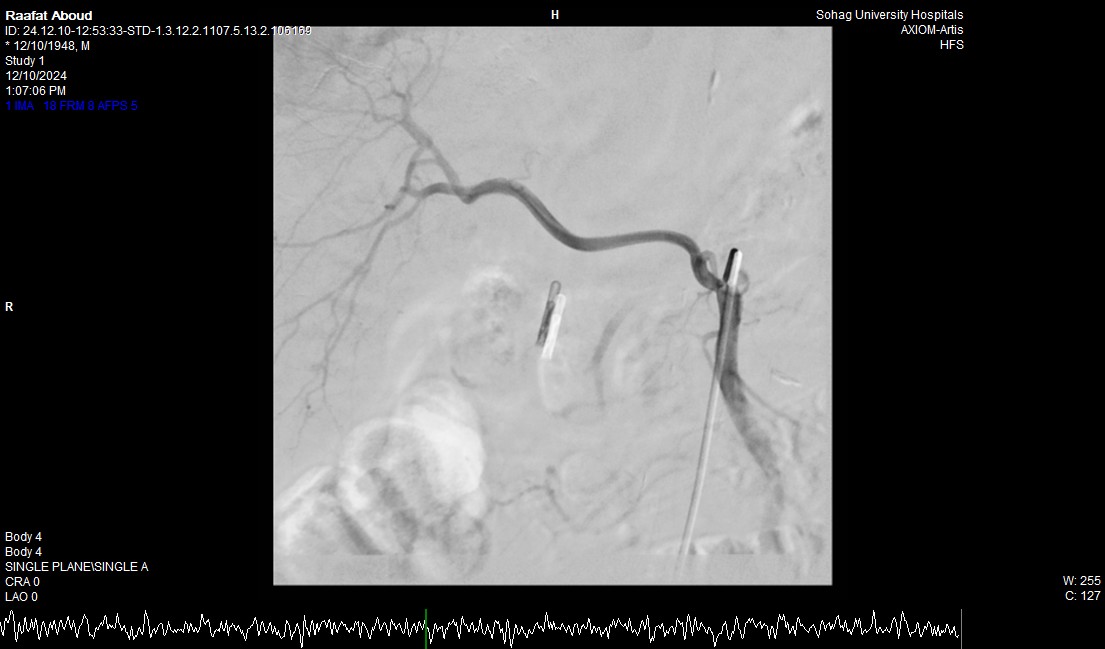

صرح الدكتور حسان النعماني رئيس جامعة سوهاج ان فريق طبي بوحدة الجهاز الهضمي والكبد بقسم الباطنة العامة ووحدة الاشعة التداخلية بقسم الاشعة نجح في انقاذ حياه مريض يبلغ من العمر ٧٥ عاماً له تاريخ مرضي ويعاني بقصور بوظائف الكلي وتليف بالكبد، حيث نجح الفريق في ايقاف نزف شرياني حاد من خلال إجراء التدخل السريع بإستخدام المنظار والقسطره الشريانيه العلاجيه بالاشعة التداخلية، مثمناً دور المستشفيات الجامعية في خدمة المرضي وما تمتلكه من الكوادر الطبية ذوي الخبرات التي تؤهلها للتعامل مع مثل هذه الحالات الطارئة باحترافية ومهارة فائقة.

وأوضح الدكتور مجدي القاضي عميد كلية الطب البشري ورئيس مجلس إدارة المستشفيات الجامعية تم التعامل علي الفور مع المريض الذي حضر الي استقبال الباطنة العامة، وكان يعاني من نزيف حاد وقيء دموي وبراز مدمم وانيميا حادة وعلاماته الحيوية غير مستقرة، وتم علي الفور حجزه بوحدة الرعاية المتوسطة لتحسين العلامات الحيوية واجراء منظار علوي عاجل له،مما يعكس التقدم الهائل في الامكانيات والفرق المدربة داخل المستشفيات الجامعية.

وأضاف الدكتور أحمد كمال المدير التنفيذي للمستشفيات الجامعية انه بعد اجراء الفحوصات للمريض تبين وجود قرحة كبيرة بالاثني عشر وشريان نازف، حيث نجح الفريق في التحكم المبدئي بالنزيف عن طريق تركيب مشبك معدني بالمنظار وحقن للقرحة النازفة، ثم تم استدعاء فريق أطباء وحدة الاشعة التداخلية علي الفور وتم عمل غلق للشريان النازف بشكل عاجل من خلال جهاز القسطرة.

وذكر الدكتور نايل عبد الحميد رئيس قسم امراض الباطنه ان هذا التدخل الطارئ لايقاف النزيف من خلال المنظار او من خلال غلق الشريان بواسطه الاشعة التداخلية جنب المريض من التعرض للحل الجراحي في هذا العمر، مشيراً الي ان المريض الآن في حالة مستقرة حيوياً وتوقف تام للنزيف وتحسن لوظائف الكلي والكبد وتم خروجه من وحدة الرعاية المتوسطة للمتابعة بالقسم الداخلي

وأوضح الدكتور محمد زاكي رئيس قسم الأشعة أن مثل هذه الحالات تعد من الطوارئ الطبية الخطيرة والتي تستوجب عمل قسطره شريانية عاجلة لغلق الشرايين النازفه مشيراً أن وحدة الأشعة التداخلية تم تزويدها بجهاز أشعه محوري متقدم لاجراء مثل هذه الحالات، وأن هذا النجاح هو نتيجة لتعاون أقسام المستشفي مع وحدة الأشعة التداخليه لتقديم خدمة مميزه للمرضي.